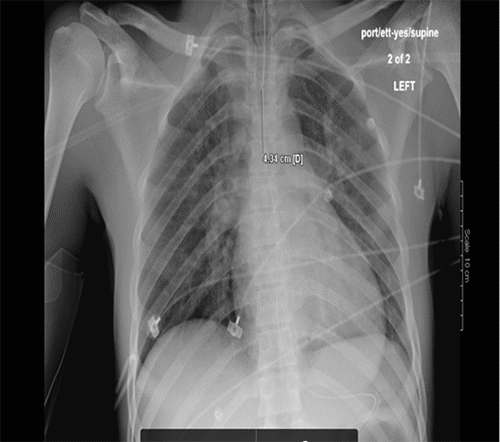

Focused assessment with sonography in trauma (FAST) revealed a diffusely hypokinetic left ventricle without tamponade or pericardial effusion. Initial chest X ray (CXR) demonstrated mild bilateral pulmonary edema (Figure 1A). CT scan of the head showed a ballistic fragment entering the left posterior parietal area, terminating in the left parasagittal anterior frontal lobe without contralateral injury (Figure 2). Imaging also revealed subarachnoid and subdural hematomas with a 3 mm midline shift.

Figure 1. Chest X-rays Illustrating Progression of NPE. Published with Permission

A.

A) Initial CXR within ten minutes of arrival shows clear lung fields

B.

B) Repeat CXR one hour later reveals marked bilateral pulmonary edema consistent with NPE

Repeat CXR less than an hour later showed worsening pulmonary edema (Figure 1B). The patient developed copious pink frothy secretions within 30 minutes. In the OR, serial bronchoscopies extracted approximately 700cc of serosanguinous fluid. He also underwent a left-sided decompressive hemicraniectomy, revealing diffuse brain edema.